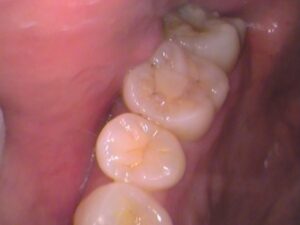

30代男性、検診で虫歯が見つかった患者さんです。

今回の場所は上の奥歯です。

今回は6番目の奥歯です。

歯を見てみましょう。

こちらの歯ですが、レジンの詰め物がされています。